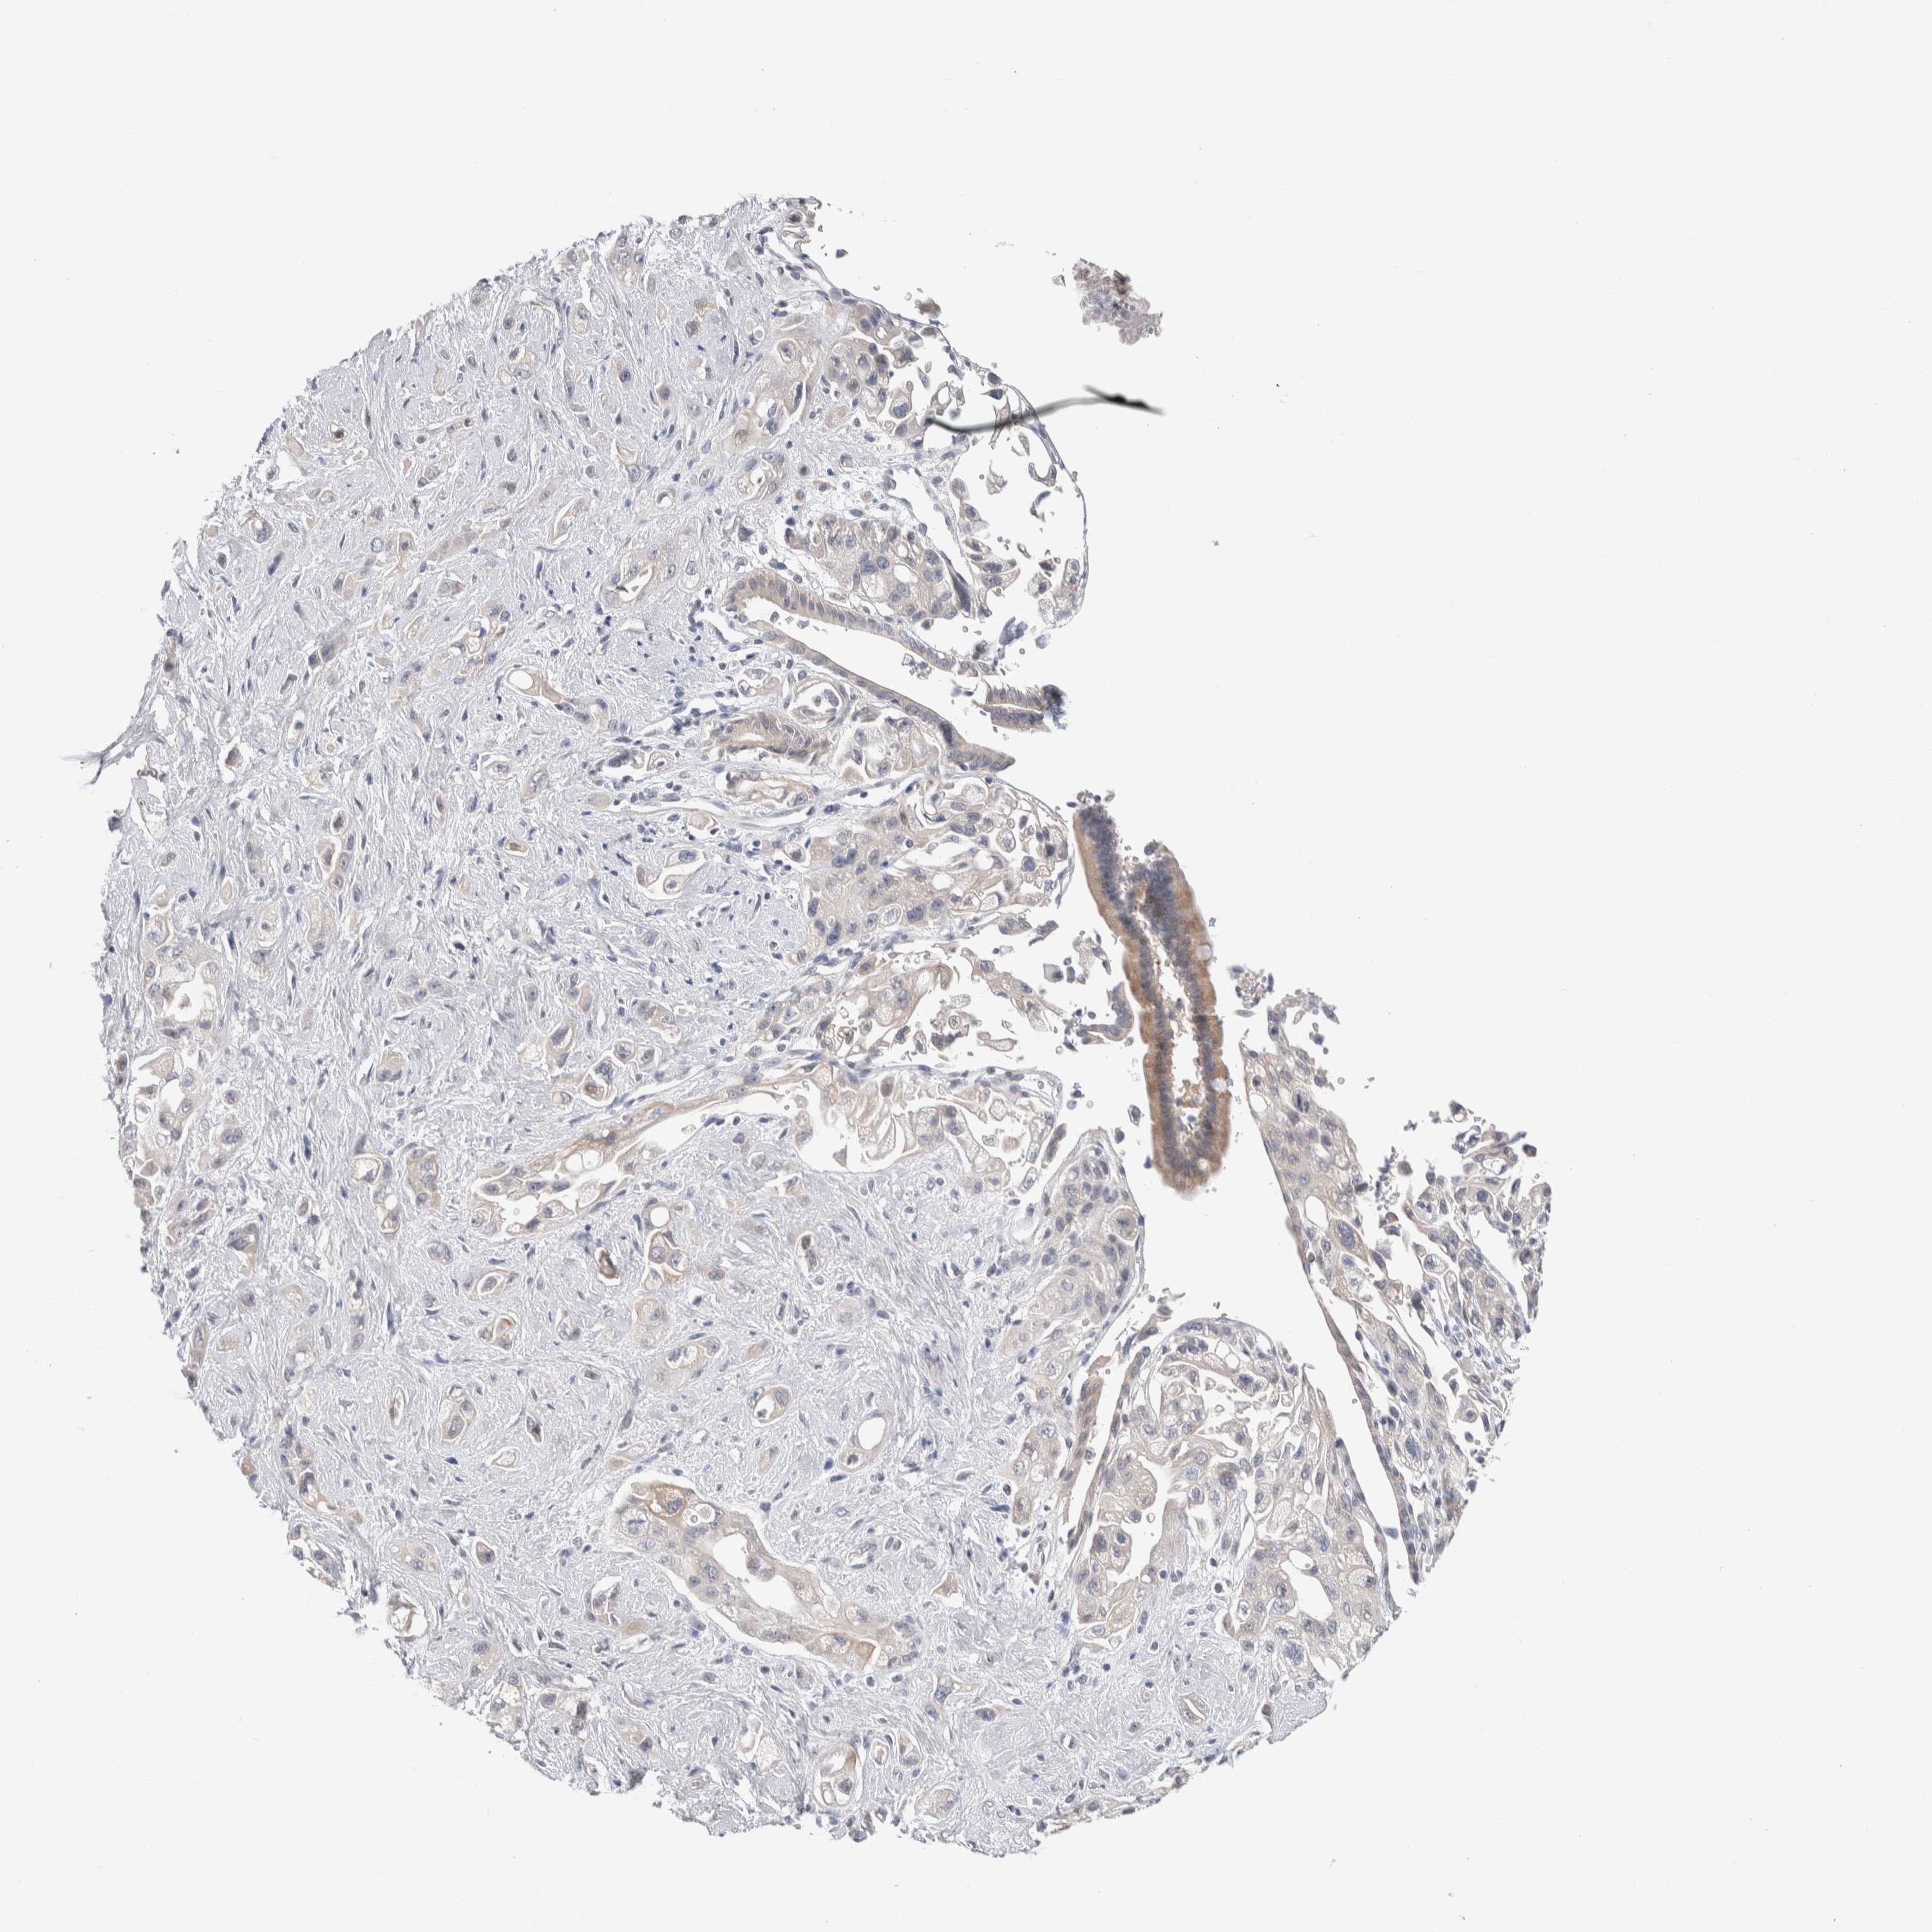

PANCREATIC CANCER - Protein expressioni

A mouse-over function shows sample information and annotation data. Click on an image to view it in a full screen mode. Samples can be filtered based on level of antibody staining by selecting one or several of the following categories: high, medium, low and not detected. The assay and annotation is described here.

Note that samples used for immunohistochemistry by the Human Protein Atlas do not correspond to samples in the TCGA dataset.

Antibody stainingi

Antibody staining in the annotated cell types in the current human tissue is reported as not detected, low, medium, or high, based on conventional immunohistochemistry profiling in selected tissues. This score is based on the combination of the staining intensity and fraction of stained cells.

Each image is clickable and will lead to virtual microscopy that enables deeper exploration of all samples and also displays staining intensity scores, fraction scores and subcellular localization as well as patient and tissue information for each sample.

Antibody HPA024406

Staining

High

Medium

Low

Not detected

Intensity

Strong

Moderate

Weak

Negative

Quantity

>75%

75%-25%

<25%

None

Location

Nuclear

Cytoplasmic/membranous

Cytoplasmic/membranous,nuclear

Adenocarcinoma, NOS